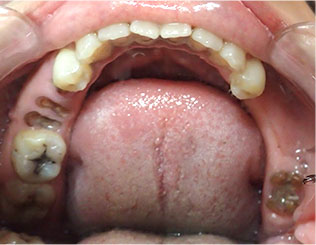

- ブリッジ 症例写真 B-0093スタンダードジルコニア9本、スタンダードジルコニア7本 男性モニターの方です。

Before

After詳細はコチラ

セラミック法によるブリッジ治療の症例

- No. B-0093

施術 スタンダードジルコニア9本、スタンダードジルコニア7本 - コメント

この方は前歯の歯並びと奥歯の虫歯、欠損の治療を希望されました。

前歯の歯並びはセラミック法で治療しました。

奥歯の欠損はブリッジで治療しました。

また、下の前歯も歯周病で1本抜歯になりましたのでその部分もブリッジ治療しています。

当院ではこの様にいろいろな歯のお悩みがあっても同時進行で治療する事が可能です。